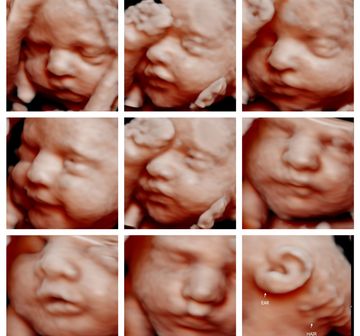

Memories that last a lifetime.